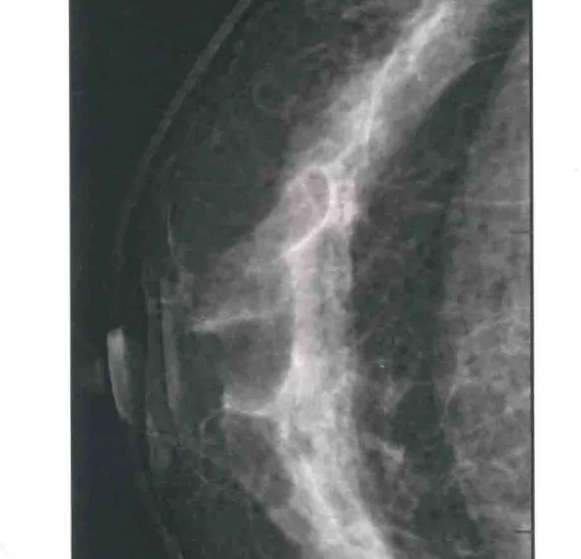

二、圖像顯示要求,含乳腺的基底部及內(nèi)外側(cè)乳腺組織,需要顯示胸肌前緣或胸壁。頭尾位與內(nèi)外斜位乳頭后線長(zhǎng)度差≤1厘米;顯示實(shí)質(zhì)后的乳腺組織,乳頭位于切線位,乳腺組織重疊;雙側(cè)乳腺頭尾位照片相對(duì)放置,則兩側(cè)乳腺呈球形;影像密度和對(duì)比度良好,能顯示0.1毫米細(xì)小鈣化,清晰沒有偽影異物、運(yùn)動(dòng)偽影和切割偽影等。